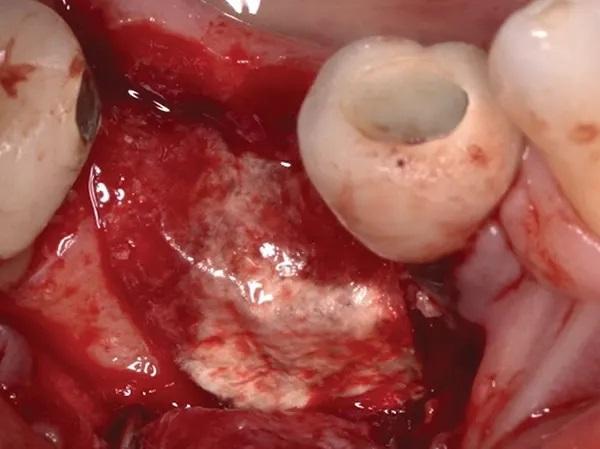

Дефект был тщательно дегранулирован и промыт физиологическим раствором. Затем была выполнена декортикация с использованием алмазного круглого бора № 6 и высокоскоростного хирургического наконечника. Два фиксирующих винта (головка винта диаметром 3 мм x хвостовик диаметром 1,5 мм x общая длина 7 мм) были помещены в дефект, чтобы закрепить аллотрансплантат и коллагеновую мембрану и добиться желаемого вертикального и горизонтального увеличения объема альвеолярного отростка (фото 7).

Фото 7. Показан кратерообразный комбинированный дефект от одной до двух стенок с двумя крепежными винтами, стратегически расположенными для натяжения мембраны и достижения идеальной высоты и ширины.